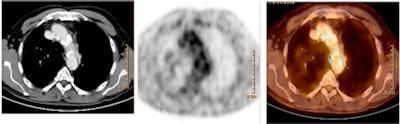

| Transaxial CT (left), FDG-PET (center), and fused PET/CT (right) of an 81-year-old male patient with significantly increased uptake in the region of the aortic arch. Calcified plaque in the aortic arch was rated as three, with a calcified plaque sum of 21. The patient experienced a myocardial infarction 14 months after the image was taken. Image courtesy of the Journal of Nuclear Medicine and the University of Munich. |

The researchers found a correlation between frequency of vascular events and patients with a target-to-background ratio ≥ 1.7 and a calcified plaque sum greater than 15. For example, 32% (9/28) of patients who had mean TBR ≥ 1.7 had cardiovascular events, compared with 2% (6/306) of patients who had mean TBR < 1.7.

For calcified plaque sum, 21% (6/28) of patients with calcified plaque sums ≥ 15 had cardiovascular events, whereas only 3% (9/306) with calcified plaque sums < 15 had events.

"The combination of a calcified plaque sum greater than 15 and a mean TBR of greater than 1.7 identified patients at highest risk for a future vascular event," the authors concluded.